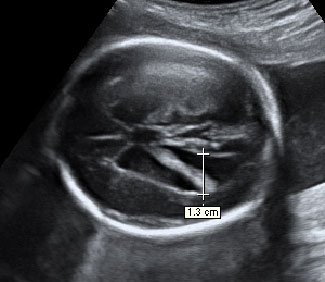

Ecografía Embarazo 2D y 3D Semana 20 - MALFORMACIONES FETALES